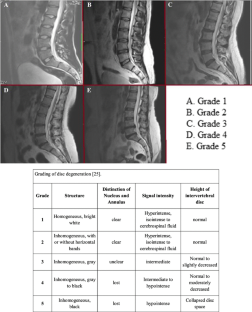

25. Pfirrmann CW, Metzdorf A, Zanetti M et al (2001) Magnetic resonance classification of lumbar intervertebral disc degeneration. Spine 26:1873–1878